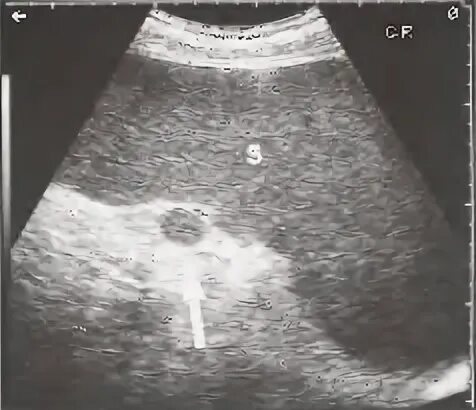

Диффузное изменение паренхимы селезенки